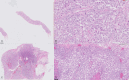

Eccrine porocarcinoma is a rare skin adnexal malignant neoplasm that may arise from a pre-existing benign eccrine poroma or without a predisposing factor. It is a highly invasive neoplasm and has a strong metastatic potential. The most frequently affected organs are the lymph nodes and rarely solid organs such as the liver, lungs and breast. We report a case of a woman with a history of surgically treated eccrine porocarcinoma that a year later presented with multiple lesions in both breasts and axillary lymphadenopathies. After a detailed imaging investigation, the diagnosis of metastatic lesions from porocarcinoma was made. To our knowledge, until the moment, only one case of breast metastasis of eccrine porocarcinoma has been reported in the literature.